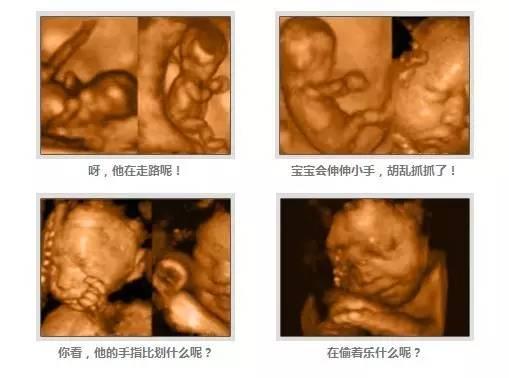

三维B超和四维B 超属于一个范畴,三维彩超和四维彩超的区别主要在于在一个“时间维度”,也就是说,三维B超是立体图片,是静态的,四维彩超是录像,是动态的,可以让孕妈妈看到胎儿一连串的动作,所以四维看起来会更清楚明了,三维彩超只能是某个时间点上的照片,四维B超的就可以做成DV那样连续的,可以刻录光盘。

(四维彩超)

三维B超和高清四维B超一样的有排畸的作用,高清四维B超更加精确。 三维B超侧重观察五脏六腑是否畸形,排除结构畸形。四维B超还观察运动神经系统是否正常,运动是否协调。